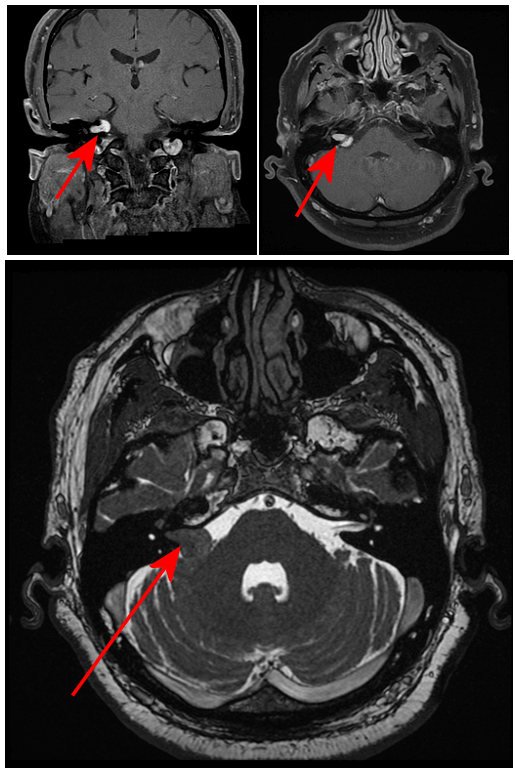

Figure 1: Yellow arrow Top row . Coronal (left) and axial (right) T1 postcontrast images demonstrate a homogenously enhancing ice cram cone shaped right cerebellopontine angle (CPA) mass extending into the internal auditory canal. Bottom Axial FIESTA (fluid sensitive volumetric acquisition) demonstrates effacement of the extra-axial fluid by the CPA mass.

Most vestibular schwannomas are avidly and homogenously enhancing although intratumoral cysts and hemorrhage may be present. The ice cream cone shape including extension into the IAC and absence of a dural tail helps distinguish vestibular schwannomas from meningiomas, the other extra-axial tumor commonly found in the CPA. Treatment includes resection, radiosurgery or observation depending on symptoms, tumor size and patient age.